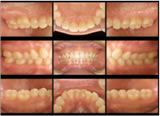

① 口腔内写真

記録として残すことで比較評価ができ、

またパソコン上で拡大してチェックできます。